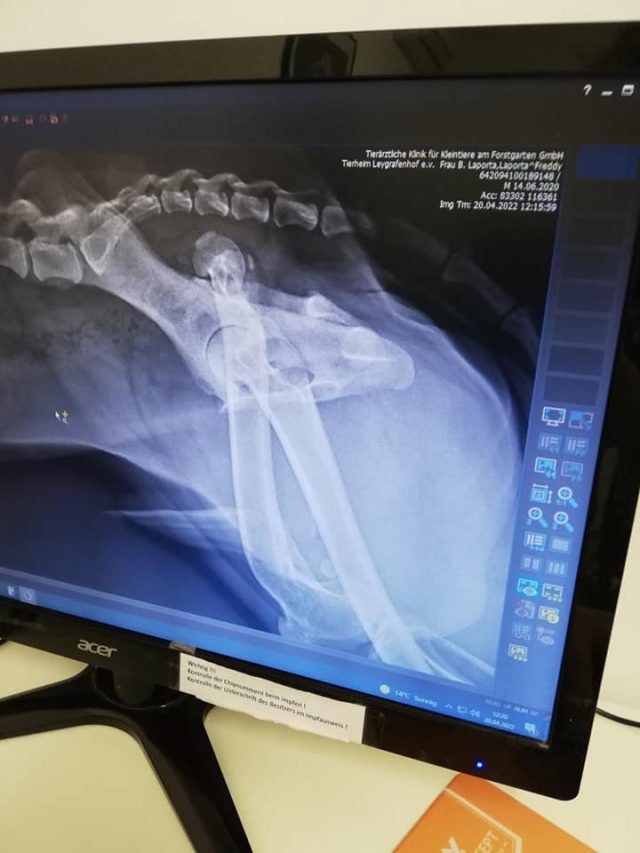

Er wurde bereits auf Herzwurm, Ehrlichiose, Borreliose und Leishmaniose getestet und alles war negativ. Doch leider wurde beim Tierarzt Check festgestellt, dass am linken Bein der Hüftknopf raus ist und dass das Knie falsch zusammen gewachsen ist. Diese Schäden scheinen schon länger vorzuliegen.